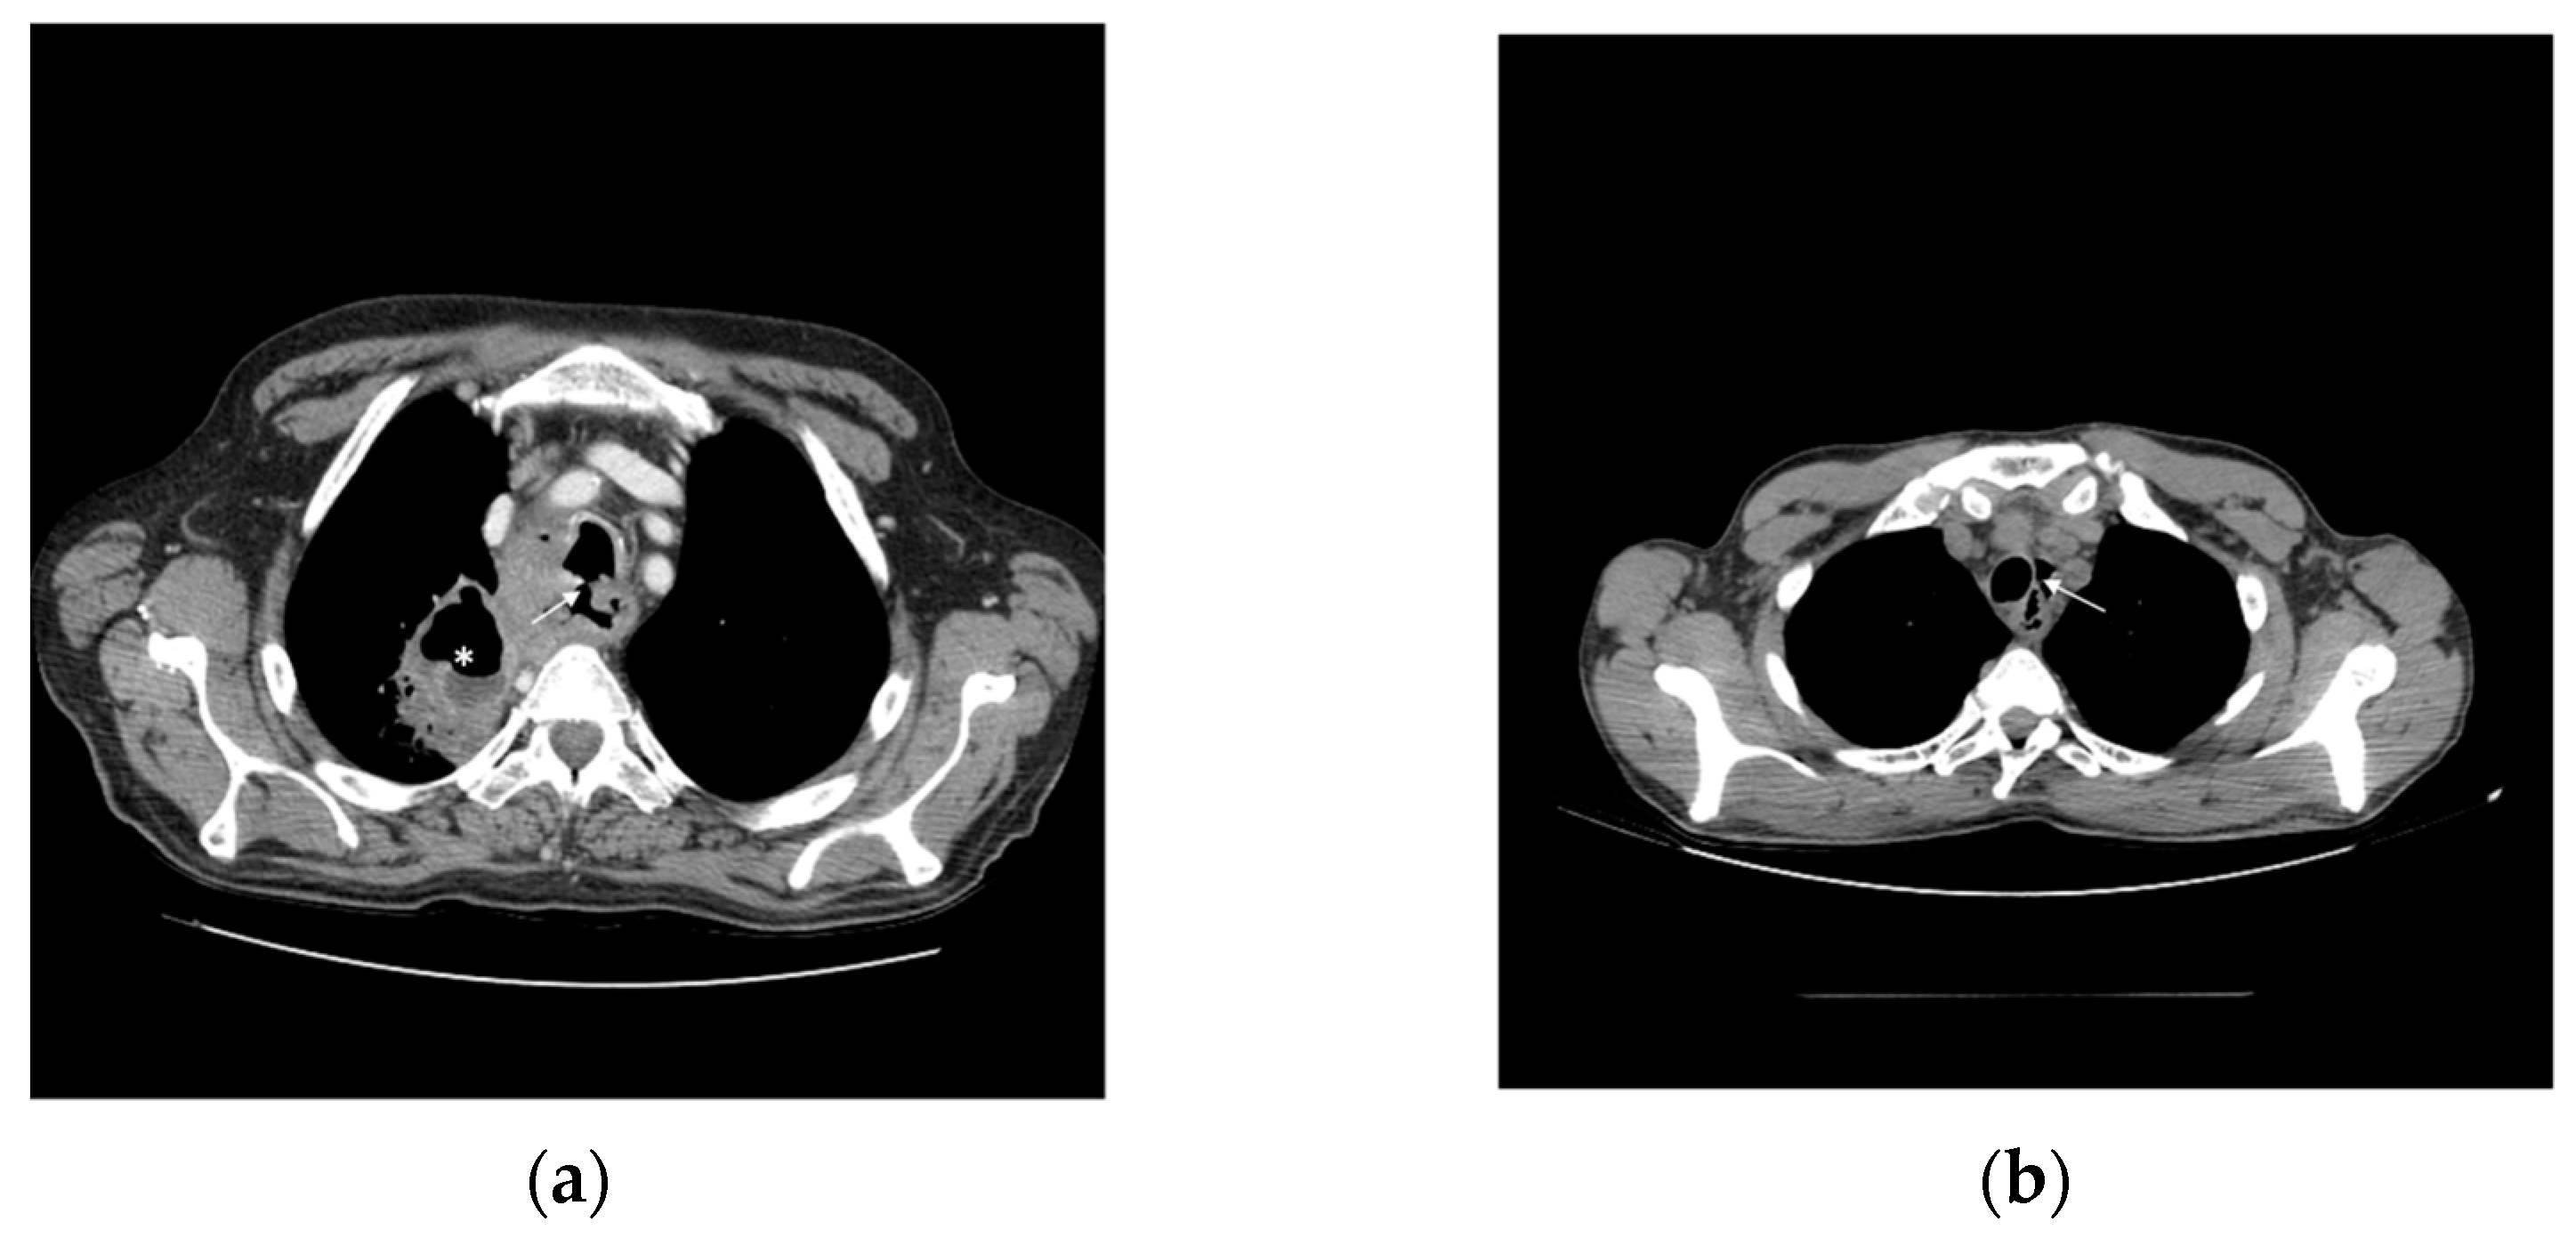

The unique anatomy of the oesophagus and close proximity to the cardiopulmonary system favours the risk of major morbidity from cancer. Oesophageal fistula develops in 5 to 20% of oesophageal cancers, most commonly between the oesophagus and the respiratory tract (Figure 2a), and occasionally to pleural space, the aorta or other mediastinal structures (Figure 2b). Apart from tumour invasion, fistulas may also develop secondarily to radiation or endoscopic therapies. A history of worsening dysphagia and dyspnea, and coughing temporally related to drinking and eating is highly suggestive of an oesophagorespiratory fistula [53,54].

Figure 2.

Oesophageal fistula. (a) Tracheo-oesophageal fistula (arrow) associated with pneumonia and lung abscess (*) (b) Squamous carcinoma of cervical oesophagus complicated with pneumomediastinum (arrow).